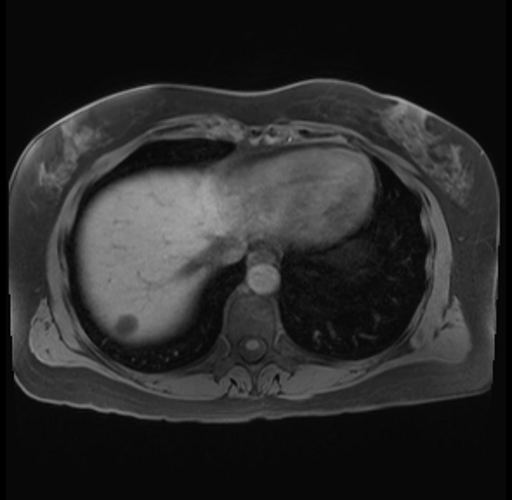

Imaging Analysis

Look through the patient's CT scan to identify any areas of concern for the necessary procedure.

Based on your CT findings, which issue(s) are present and would give reason for "planned slowing down moment(s)" in this case?

Considering a standard distal pancreatectomy procedure, what step(s) of the operation would you do differently in this case?